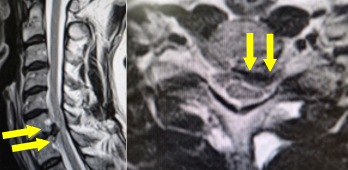

手術前のMRIでは、第6/7椎間の椎間板が脊柱管へ飛び出し、脊髄を強く圧迫しています。

手術により、飛び出した椎間板を前方から摘出し、人工スペーサーと金属製のプレートなどで上下の骨を固定しました。術後、神経症状は著明に改善し、MRIでも脊髄の圧迫が解除されています。